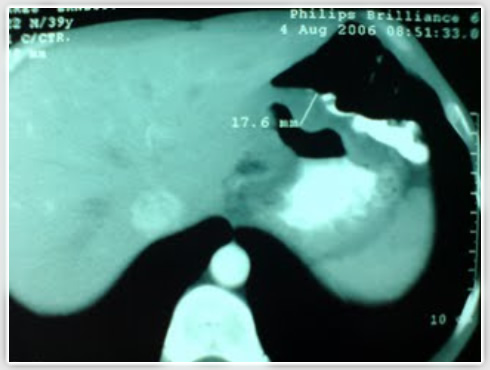

TAC que muestra cáncer gástrico infiltrativo

En el caso de la tomografía axial computarizada, no todos los cánceres van a poder ser detectados. Solo lo serán aquellos avanzados de mas de 2 cm de diámetro especialmente si el estomago se encuentra bien distendido. Los carcinomas infiltrativos son mas evidentes y son mas fácilmente detectables dado el engrosamiento de las paredes asociado a una menor distensión de la cámara gástrica.

El objetivo en últimas de la tomografía en cáncer gástrico es la estatificación tumoral en cáncer avanzado resaltando el compromiso extra gástrico de la masa facilitando con esto la decisión de llevar a cirugía o no a este tipo de pacientes. Por otro lado es la ultrasonografía endoscópica la que permite evaluar la extensión de los canceres tempranos. |